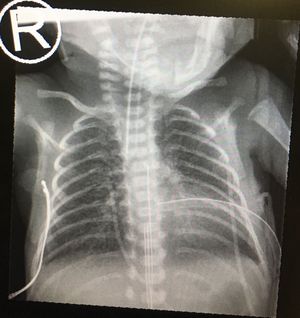

Chest xray nicu hyper expanded

26 w c hyper-expanded lungs 10 rib count with flat a diaphragm. Bb has PIE, on hfo ventilation. The map was decreased and bb left stable. ETT looks low but head position wasn’t optimal. Uva lines good position. No pneumothorax.